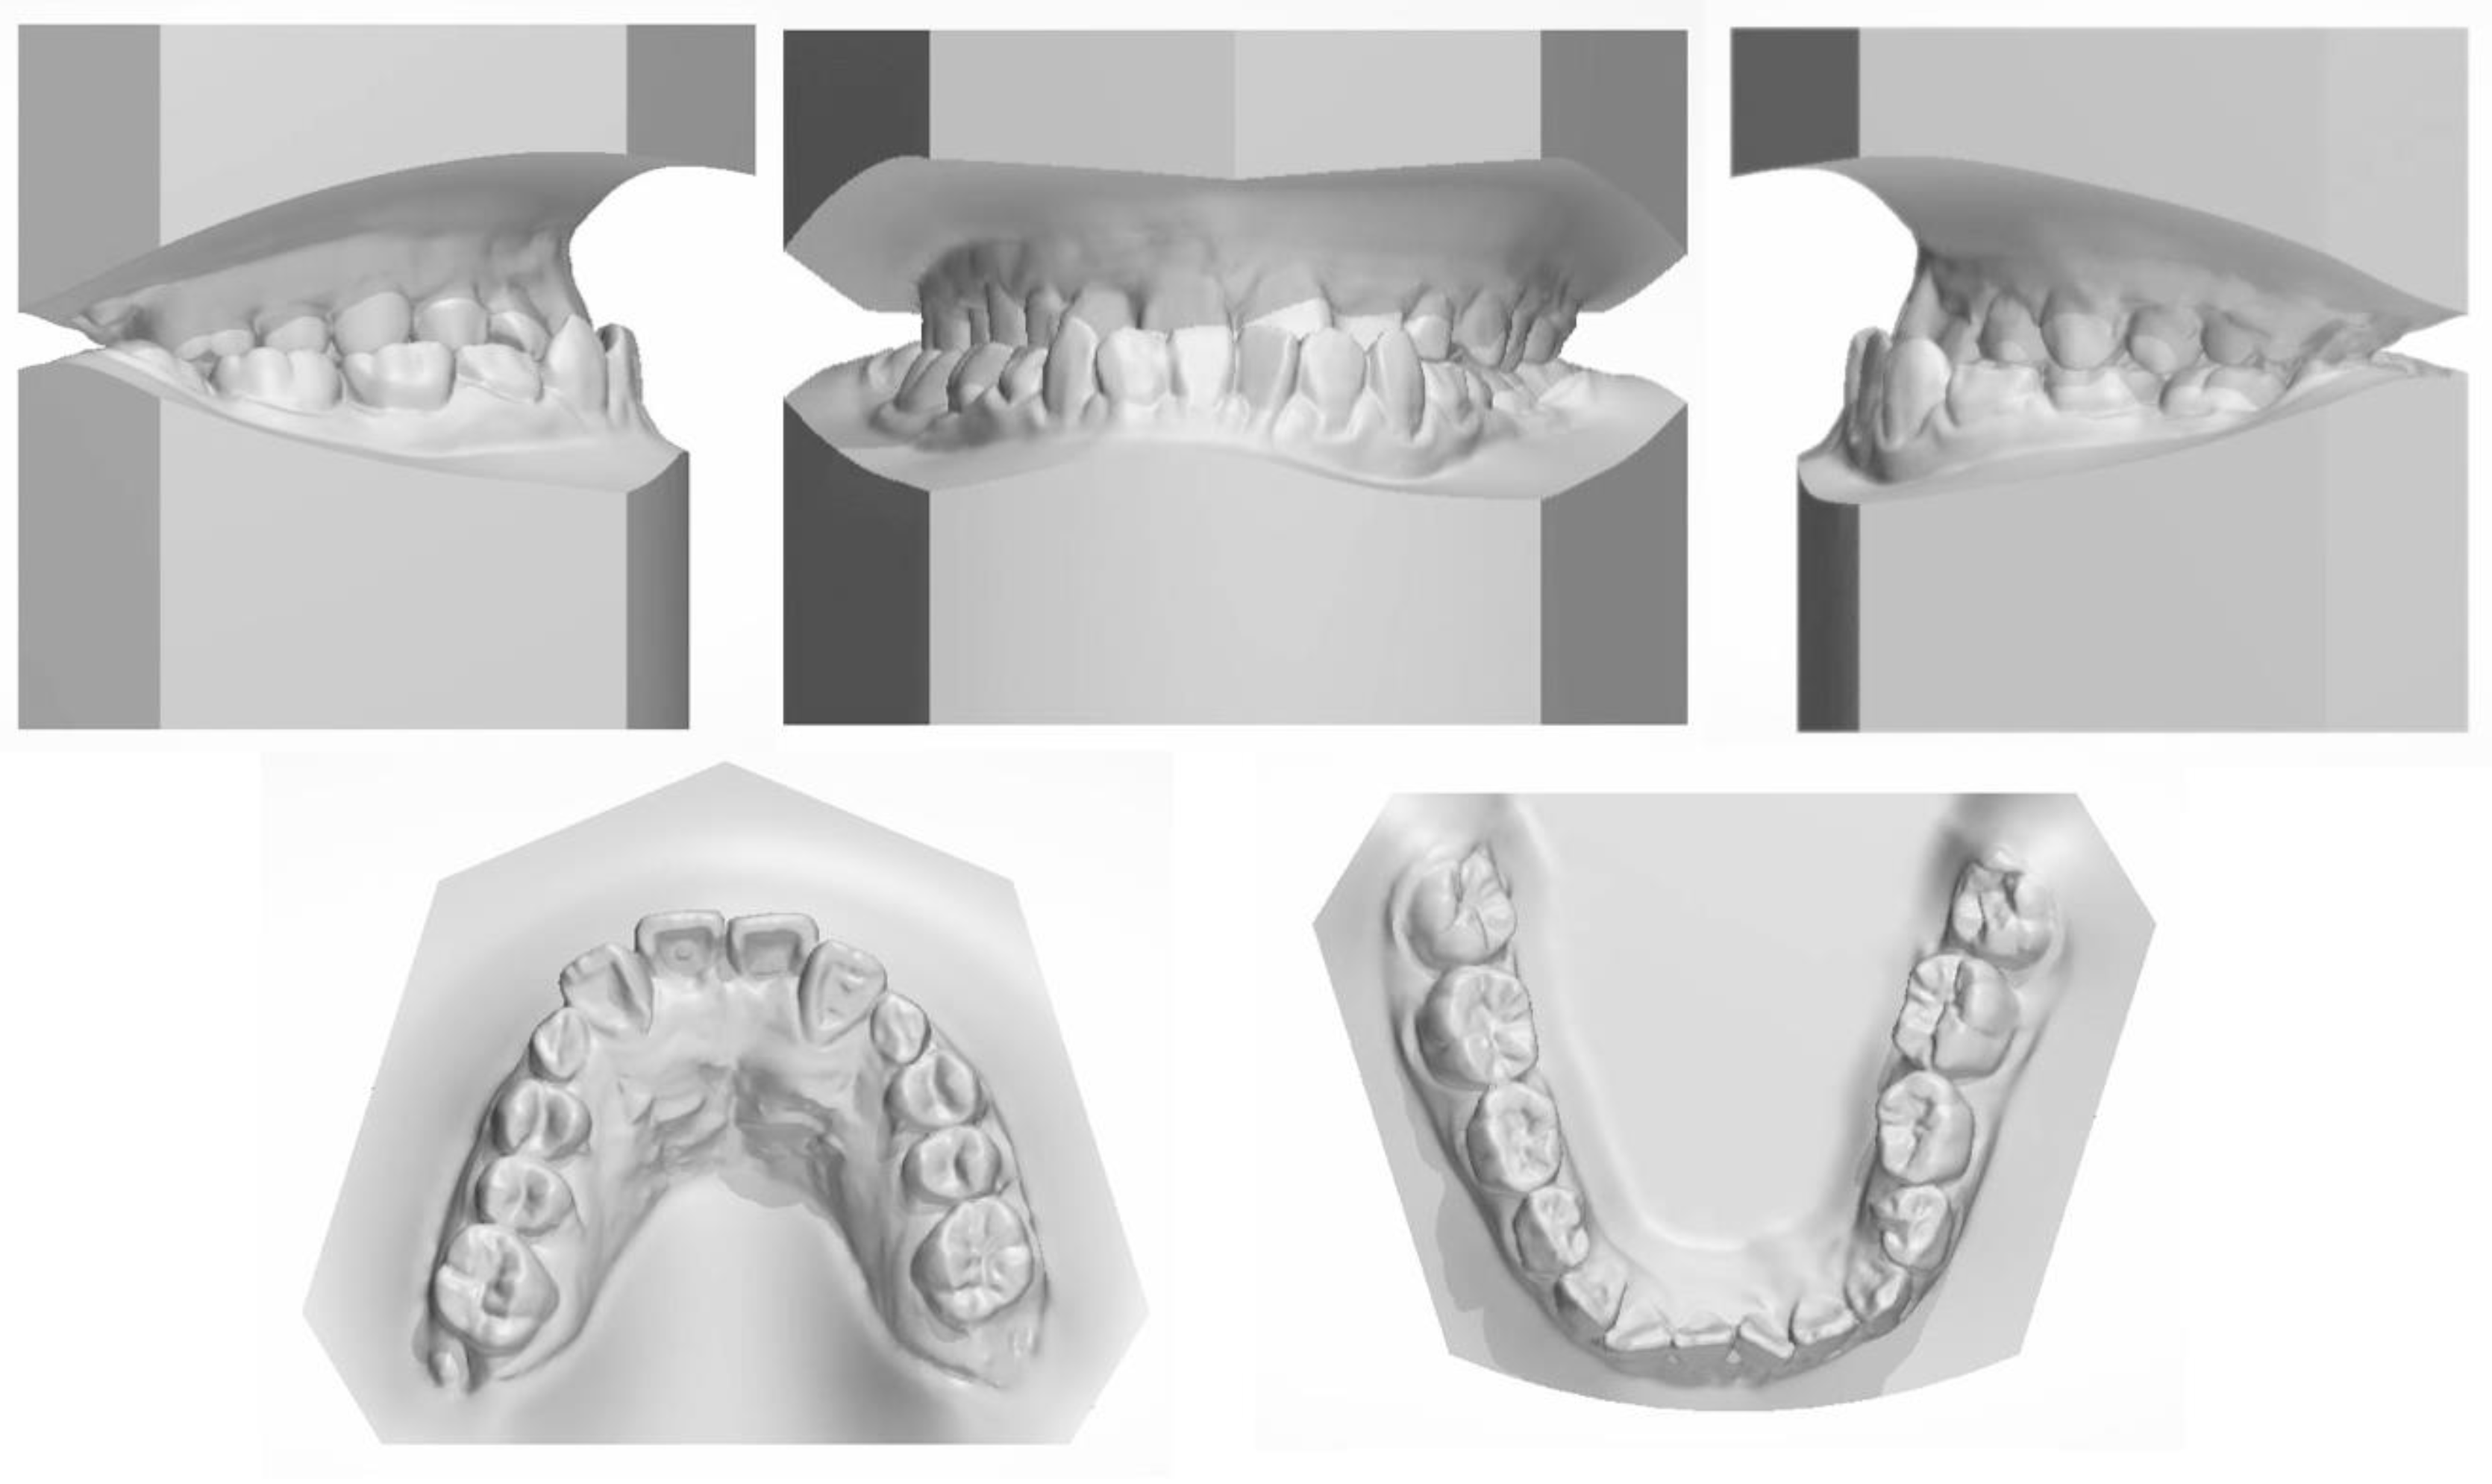

Figure 2. The pretreatment dental cast.

The facial examination displayed a concave profile, a prominent chin, an increased lower third of the face, and an unconfident smile. The upper lip was retruded 4.8 mm in relation to the E plane (Figure 1). The intraoral photographs (Figure 1) and dental casts (Figure 2) showed a bilateral Class III molar relationship and an anterior crossbite with a negative overjet of 2 mm. The width of the maxilla was narrow compared to the mandible, which led to a crossbite in the right posterior region and a compensatory lingual inclination in the left mandibular posterior region. All the mandibular deciduous molars and maxillary deciduous canines were retained with the left permanent maxillary canine erupted labially. Scalloped thin gingiva was evident in the mandibular anterior region with an obvious root shape. Temporomandibular disorder symptoms or bad oral habits were not detected. The mandible cannot retreat to the edge-to-edge occlusion.

All the initial treatment objectives, including occlusion, periodontal health, and facial esthetics, were achieved by a satisfactory multidisciplinary approach, partly due to the cooperation of the patient. The facial photographs showed a pleasant profile and a harmonious smile. The patient was satisfied with the facial improvement, and she became more confident (Figure 7). Posttreatment intraoral photographs and dental casts (Figure 8) showed bilateral Class II molar and Class I canine relationships with an ideal overjet and overbite. The gingiva tissue in the mandibular anterior region was evidently augmented, which indicated lower periodontal risks.